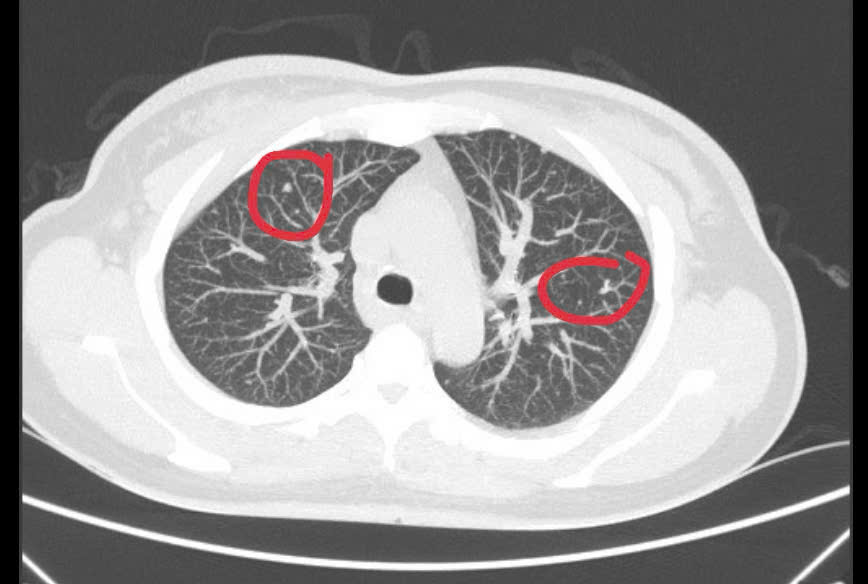

Theo bác sĩ Duy Anh, kết quả khám lâm sàng và chụp CT-scan toàn thân của bệnh nhân phát hiện có khối u vú phải kích thước 25x52mm, nhiều hạch to tròn, phổi hai bên có các nốt mờ ở màng phổi.